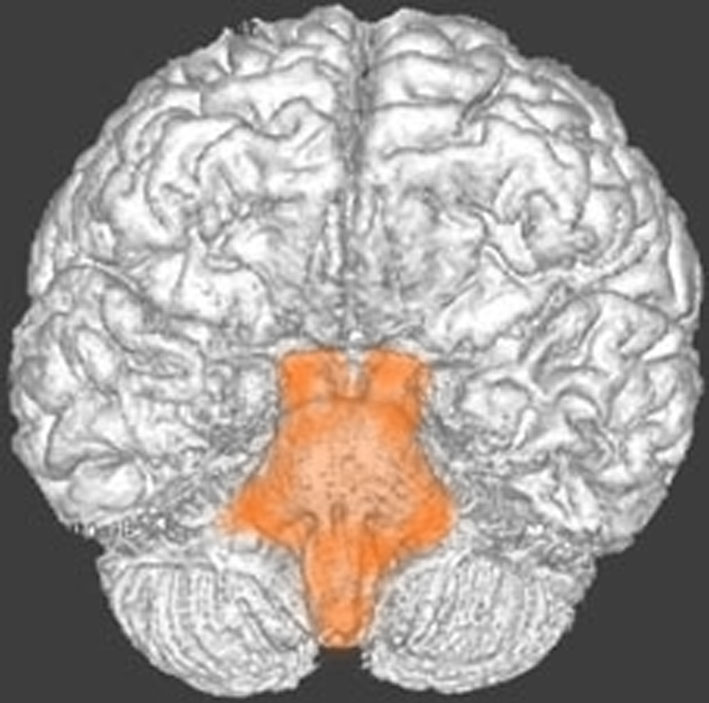

脳幹部の解剖図

- 脳の底面からしか見えないのでいろいろな角度から見ています

これは脳の中心部を縦切りにした写真です。脳幹部は上から順に,中脳 midbrain (黄色),橋 pons(オレンジ),延髄 medulla oblongata(ピンク)と呼ばれます。